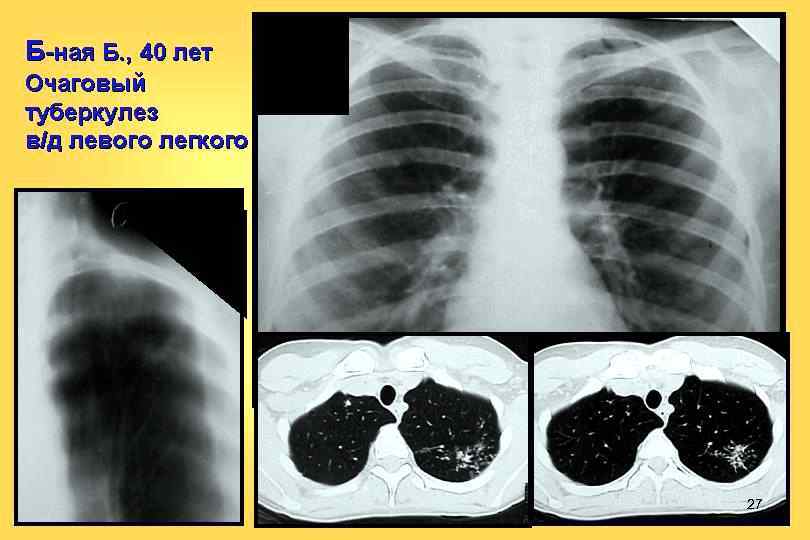

27